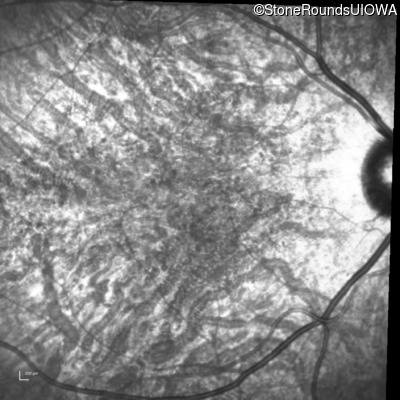

Infrared Fundus Photograph - Right - 20/40 -1

Exemplar